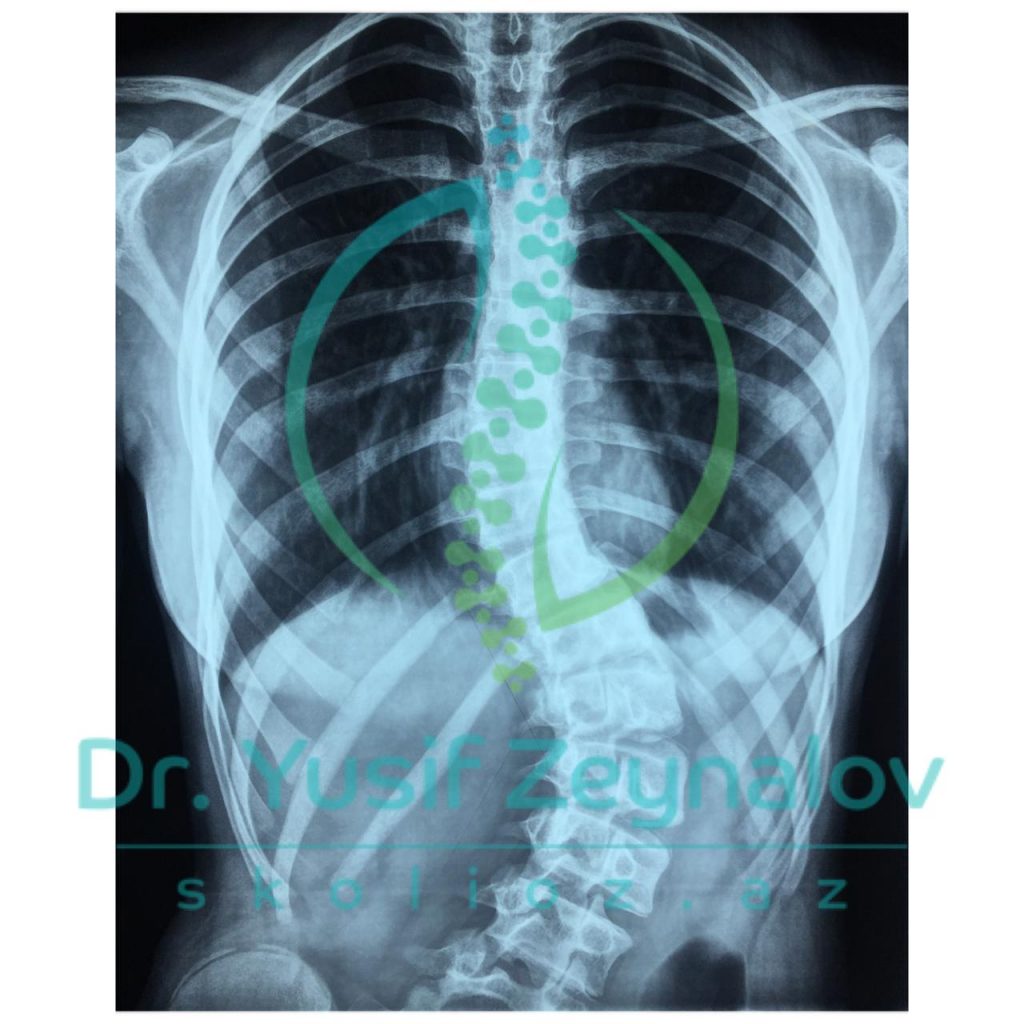

İDİOPATİK SKOLİOZ. LUMBAR DEFORMASİYA. COBB BUCAĞI 65°